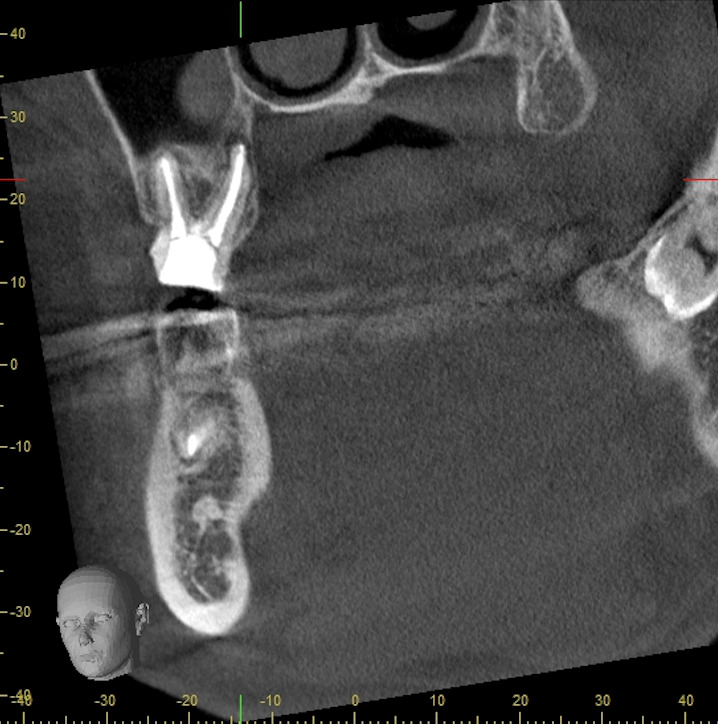

抜歯と診断されていた歯をマイクロエンド治療で保存した症例

治療概要 マイクロエンド・根管治療 再治療を繰り返していたが痛み腫れが引かず骨吸収も大きく抜歯と診断された歯をマイクロエンド治療によって病巣を縮小させ保存した。 治療費用(税込)・期間 165,000円(自 […]

精密根管治療により抜歯を回避し、歯を保存した症例

患者様情報 40代男性 患者様のお悩み 奥の歯茎が疼く 治療概要 根管治療 提案内容 CTを撮影したところ、根管治療が不十分な部分があり、歯の根の先端に細菌の膿が確認される状態でした。再度の根管治療が必要な状態でしたので […]